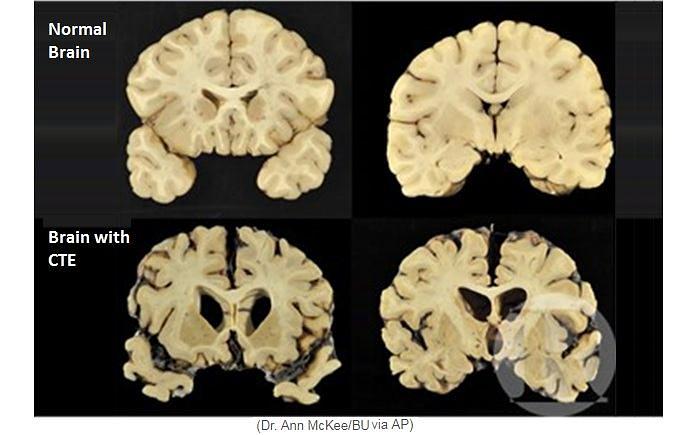

Gehirnschäden im Sport

Aufklärung für Fußballvereine, Kampfsport Vereine, Boxvereine, American

Football Vereine und Schulsport zu Chronische Traumatische

Encephalopathie, wo in Deutschland leider noch immer zu wenig...